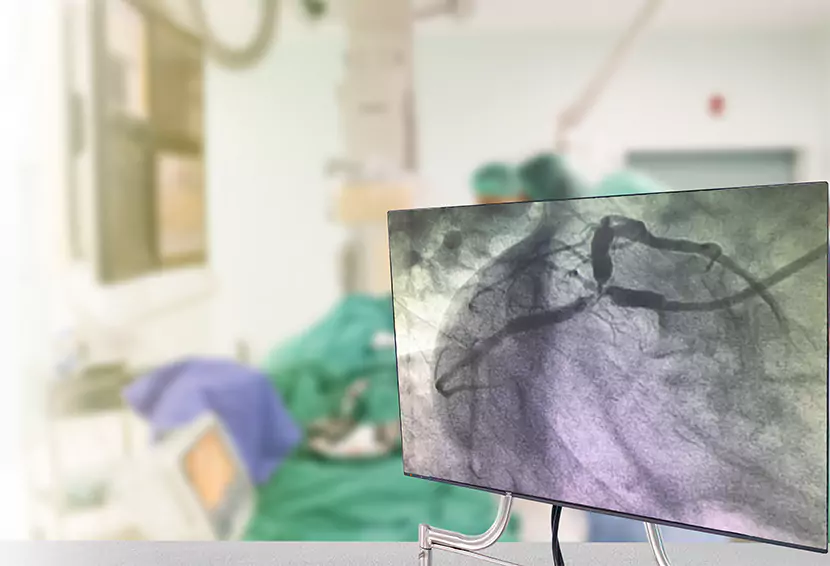

• Doctors use detailed imaging guidance and a guidewire to carefully move the catheter towards the blocked section of the peripheral artery.

• Once the catheter is in the right position. Doctors carefully inflate the balloon, to open the blocked artery and restore the flow of blood. If doctors feel the need, a stent may be implanted within the affected section of the artery to prevent any blockage in future.